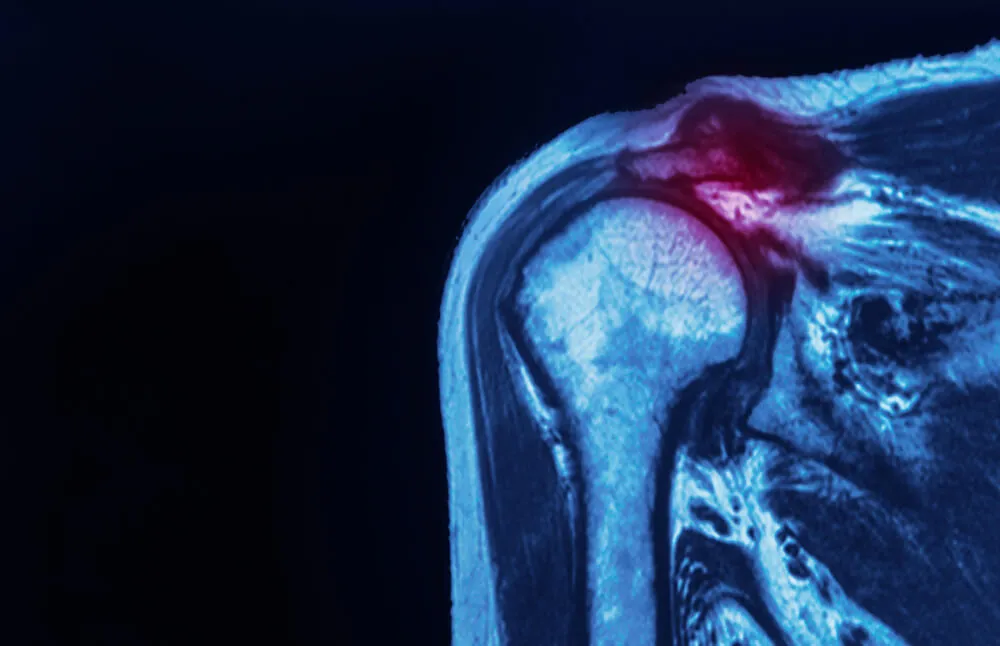

Labral Tear – the cartilage structure that lines the glenoid (cup) of the shoulder is often damaged by the dislocation.

Rotator Cuff Tears – tearing of the tendons that make up the rotator cuff is common as they are stretched forcefully during a dislocation.